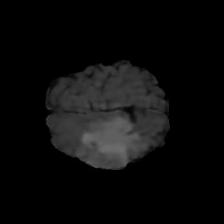

Brain tumor segmentation. Segmenting tumors in brain is challenging due to the high variance in appearance and shape of the tumors [28]. We use a subset of the 2017 Brain Tumour Image Segmentation (BraTS) dataset [29, 26]. It contains multi-parametric 3D MRI scans. The segmentation masks include (possibly overlapping) three classes of tumor. The 3D scans are split into 2D image slices, and only images that contain at least one tumor class are retained. Figure 7 shows three MSGNet generated samples as well as the corresponding masks. Since MSGNet adheres to the underlying relationships between various classes, we see that the generated images and the masks for different tumor classes are in line with the images and masks from the training set. In general, MSGNet rarely generated erroneous samples; we found roughly one sample per 3000 generations that could be rejected. Similar to the malaria experiment, we observed an improvement of 3.1% () in -score on the validation set.

A subset of the BrATS dataset was used. We used the images accompanied by segmentation layouts from the FLAIR and T1Gd modes. The segmentation layouts showed the sub-regions for three different classes: GD-enhancing tumor, the peritumoral edema, and the necrotic and non-enhancing tumor core. The brain and the background were treated as an additional class. We refer to [32] for further details. For the two modes, the background has been modelled using two different classes. We only considered half of the 155 slices, i.e., we took only the even-numbered slices and out of those we discarded the slices that did not include one of the previously mentioned tumor-classes in order to create a more balanced dataset. This resulted in 20,000 images that were further augmented with 6,000 MSGNet generated images. Example generations of the masks as well as the images are shown in Figure 12.